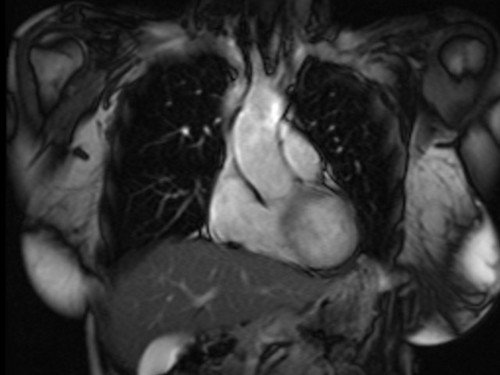

heart mri localizer 2 - MRI